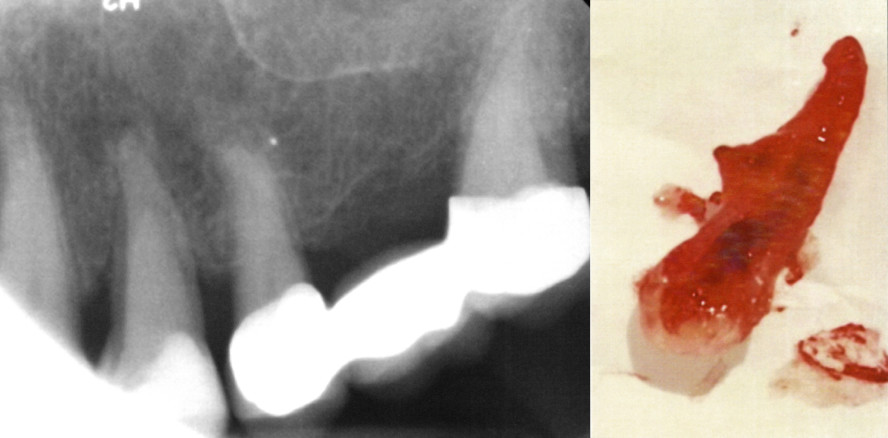

„Hemisektion“ eines oberen ersten Prämolaren

Implantat oder Zahnerhaltung? Jeder Patient und Zahnarzt stellt sich immer wieder aufs Neue dieser Frage, wenn eine Extraktion anzustehen droht. Die Längsfraktur eines oberen ersten Prämolaren bereitete einer Patientin des Autors nicht nur Schmerzen, sondern machte ihr auch Angst, wie die nach einer eventuellen Extraktion dieses Zahnes entstehende Lücke zu schließen wäre. Die Entfernung der palatinalen Wurzel wurde notwendig und der nachfolgende Erhalt der bukkalen Wurzel konnte (bisher) weitere umfangreiche, prothetische und/oder implantologische Korrekturen, aber auch ästhetische Beeinträchtigung verhindern. Möglicherweise handelt es sich (nur) um eine semipermanente Erhaltungsmaßnahme.

Am 18. November 2016 stellte sich die Patientin mit Schmerzen am Zahn 24 vor. Zunächst wurde vermutet (gehofft), es handele sich lediglich um den frakturierten palatinalen Anteil der klinischen Krone, der weder intensiven Kontakt zum Limbus alveolaris haben möge noch nach seiner unkomplizierten Entfernung Probleme beim Rekon­struieren des Zahnes nach der endodon­tischen Bearbeitung machen würde. Nach Mobilisierung dieses (vermeintlichen) ­Höckers entleerte sich spontan eine große Menge Pus aus dem Spalt zwischen den palatinalen und bukkalen Kronenanteilen. Die Fraktur schien tiefer zu reichen, als angenommen. Nach Anästhesie sollte dieses Frakturstück entfernt und die verbliebene Kronensubstanz eingehender betrachtet werden. Es stellte sich bald heraus, dass dieser Prämolar glücklicherweise zwei deutlich ausgeprägte Wurzeln hatte und der bukkale Wurzelkanal bei der Extraktion des palatinalen Zahnanteils nicht längs eröffnet worden war. Die bukkale Wurzel hatte einen Lockerungsgrad (LG) II. Um den Kofferdamgummi sicher und dicht anlegen zu können, musste zuvor ein präendodontischer Kompositaufbau (frei modelliert) angefertigt werden.

Die Aufbereitung des Kanals erfolgte bis zur #40. Mit dem adhäsiven Verschluss/Aufbau wurde zeitgleich ein Glasfaserstift eingebracht. Der Restzahn wurde ein wenig außer Kontakt genommen, das palatinale Wurzelfach von Granulationsgewebe befreit. Bei der Wundkontrolle am nächsten Tag gab die Patientin lediglich leichte Wundschmerzen an. Der Zahn 24 wurde mit dem Eckzahn in einer semipermanenten Schienung verblockt.

Die Röntgenkontrollaufnahme im April 2017 zeigte deutliche Heilungstendenz des apikalen und marginalen Parodonts. Am Tage der Präparation wurde das marginale Parodont, das trotz guter häuslicher Pflege entzündet war (BOP sowie geringe Pusentleerung) mit dem Vector-System (DÜRR DENTAL SE) und PACT® (Cumdente) bearbeitet. Die Region war zum Zeitpunkt der Kroneneingliederung zwei Wochen später fast vollständig entzündungsfrei. Auch an diesem Tage wurde nochmals mit dem Airscaler und PACT® gearbeitet. Der Zahn hatte einen LG I.

Das Röntgenkontrollbild am 28. August 2017 zeigte sich in Heilung befindende parodontale Verhältnisse (apikal und marginal). Die Kontrollaufnahme ein Jahr nach der Wurzelkanalbehandlung zeigt vollständige apikale Ausheilung, jedoch war die Verblockung frakturiert. Die Lockerung des Zahnes war aber nur ein wenig mehr als physiologisch. Dennoch wurde eine neue Verblockung zwischen 23 und 24 angelegt.